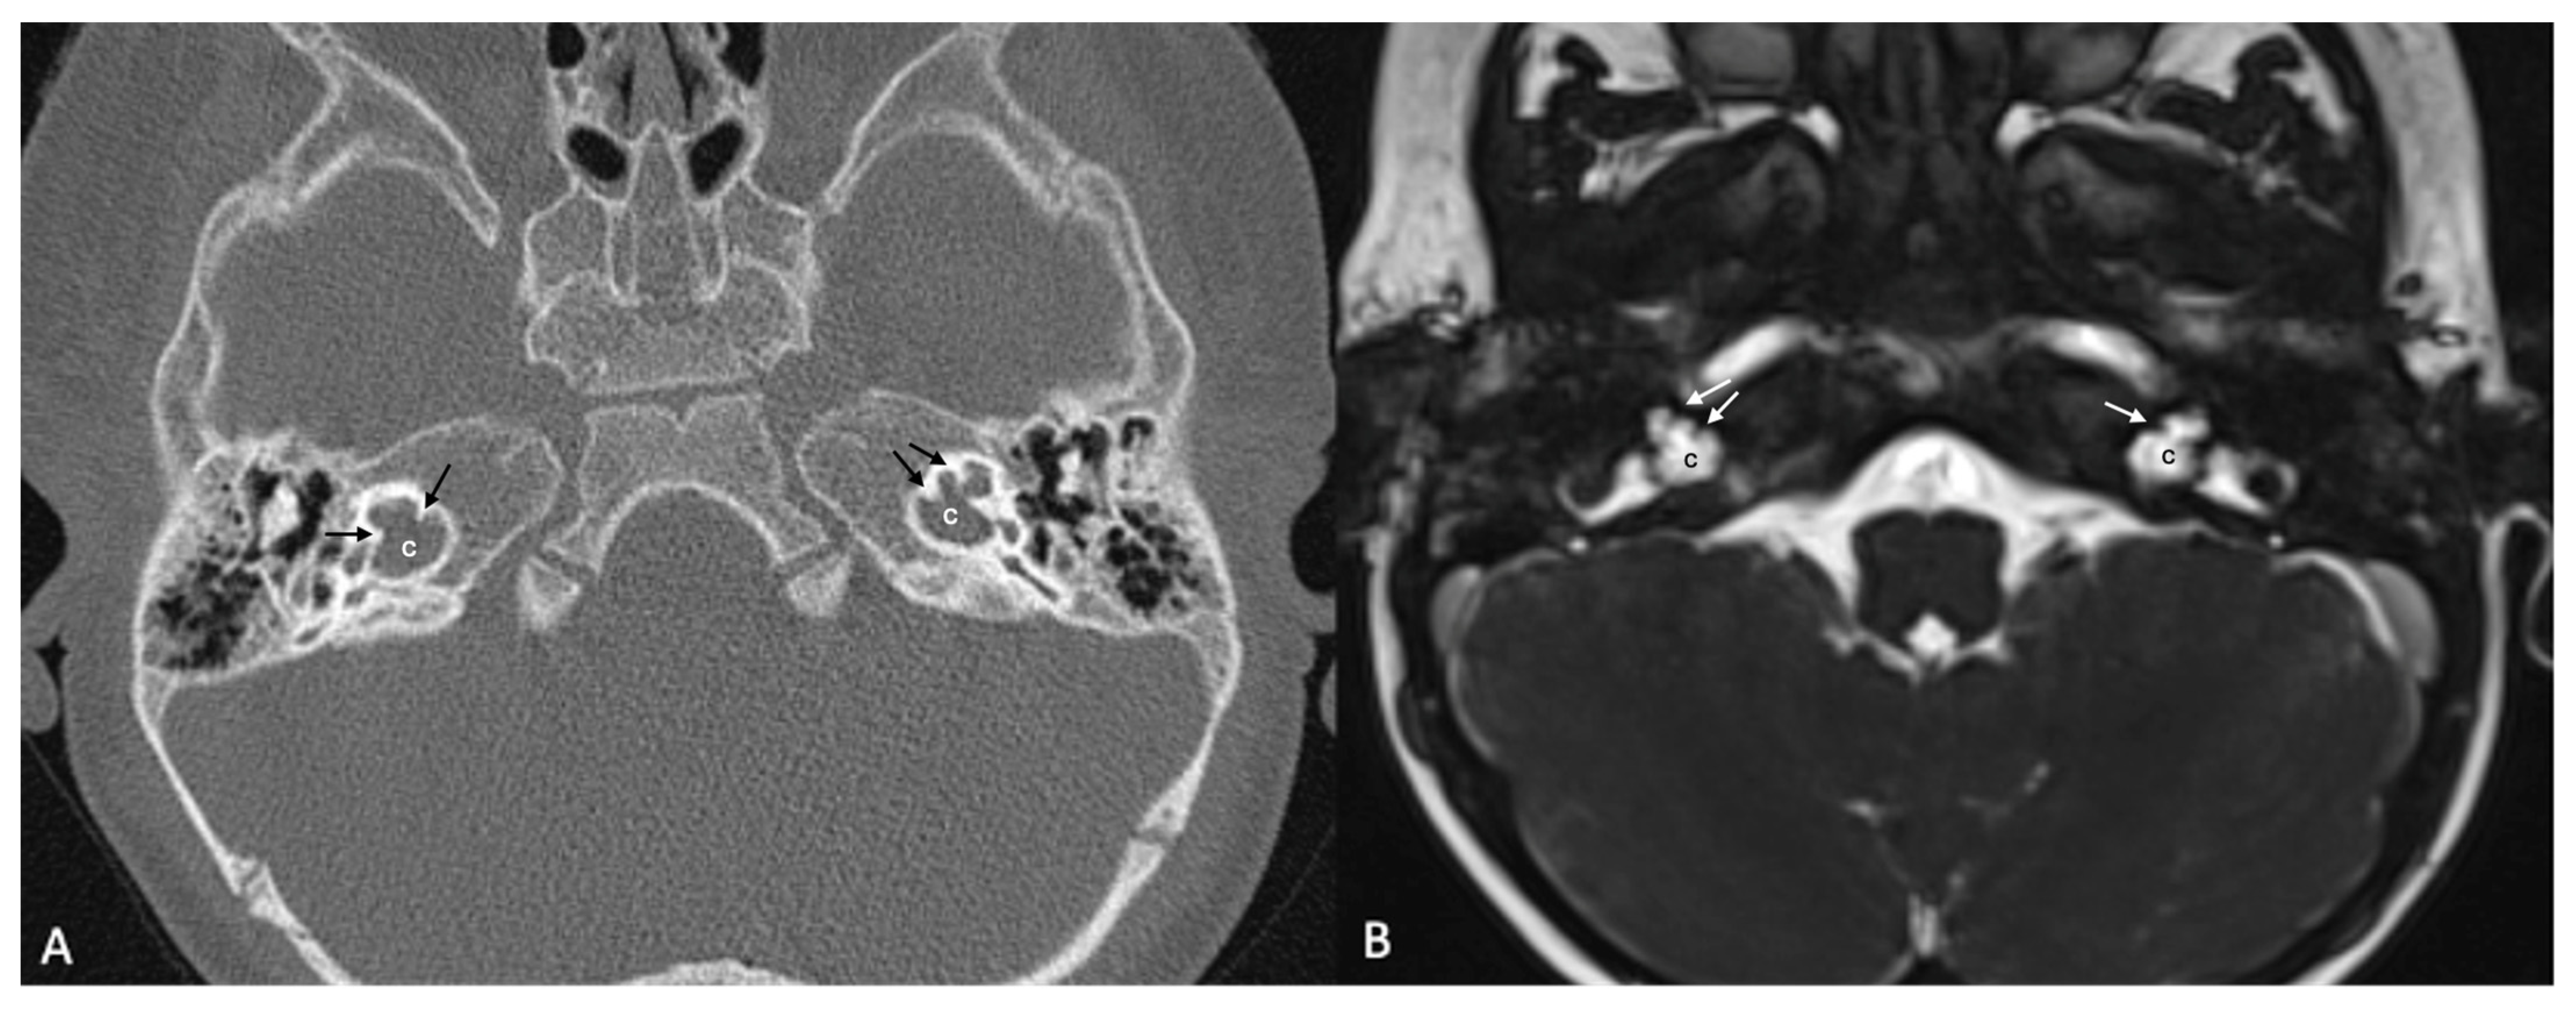

Figure 4.

(A) CT and (B) MRI images of a case of bilateral IP-3 (incomplete partition type-3). Note that despite the relative preservation of the outer contour of both cochleae (c) and the presence of interscalar septae (black and white arrows), the inner structure is featureless and the modiolus is absent.